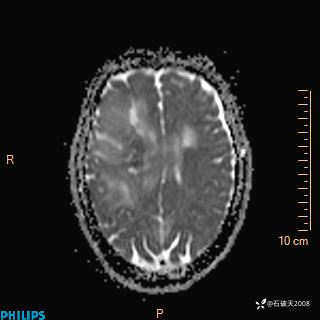

2024.2.21MR

增强轴位